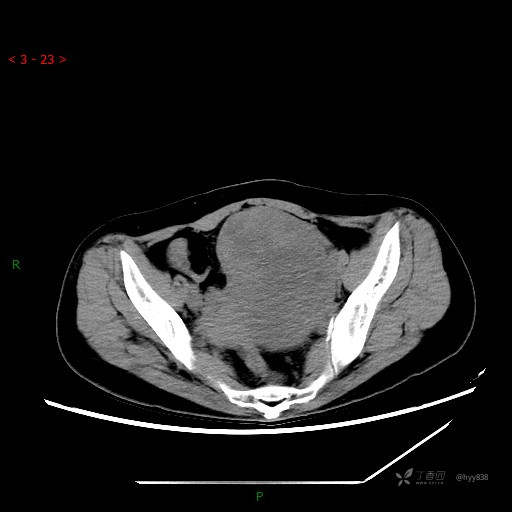

辅助检查:CT

静脉期